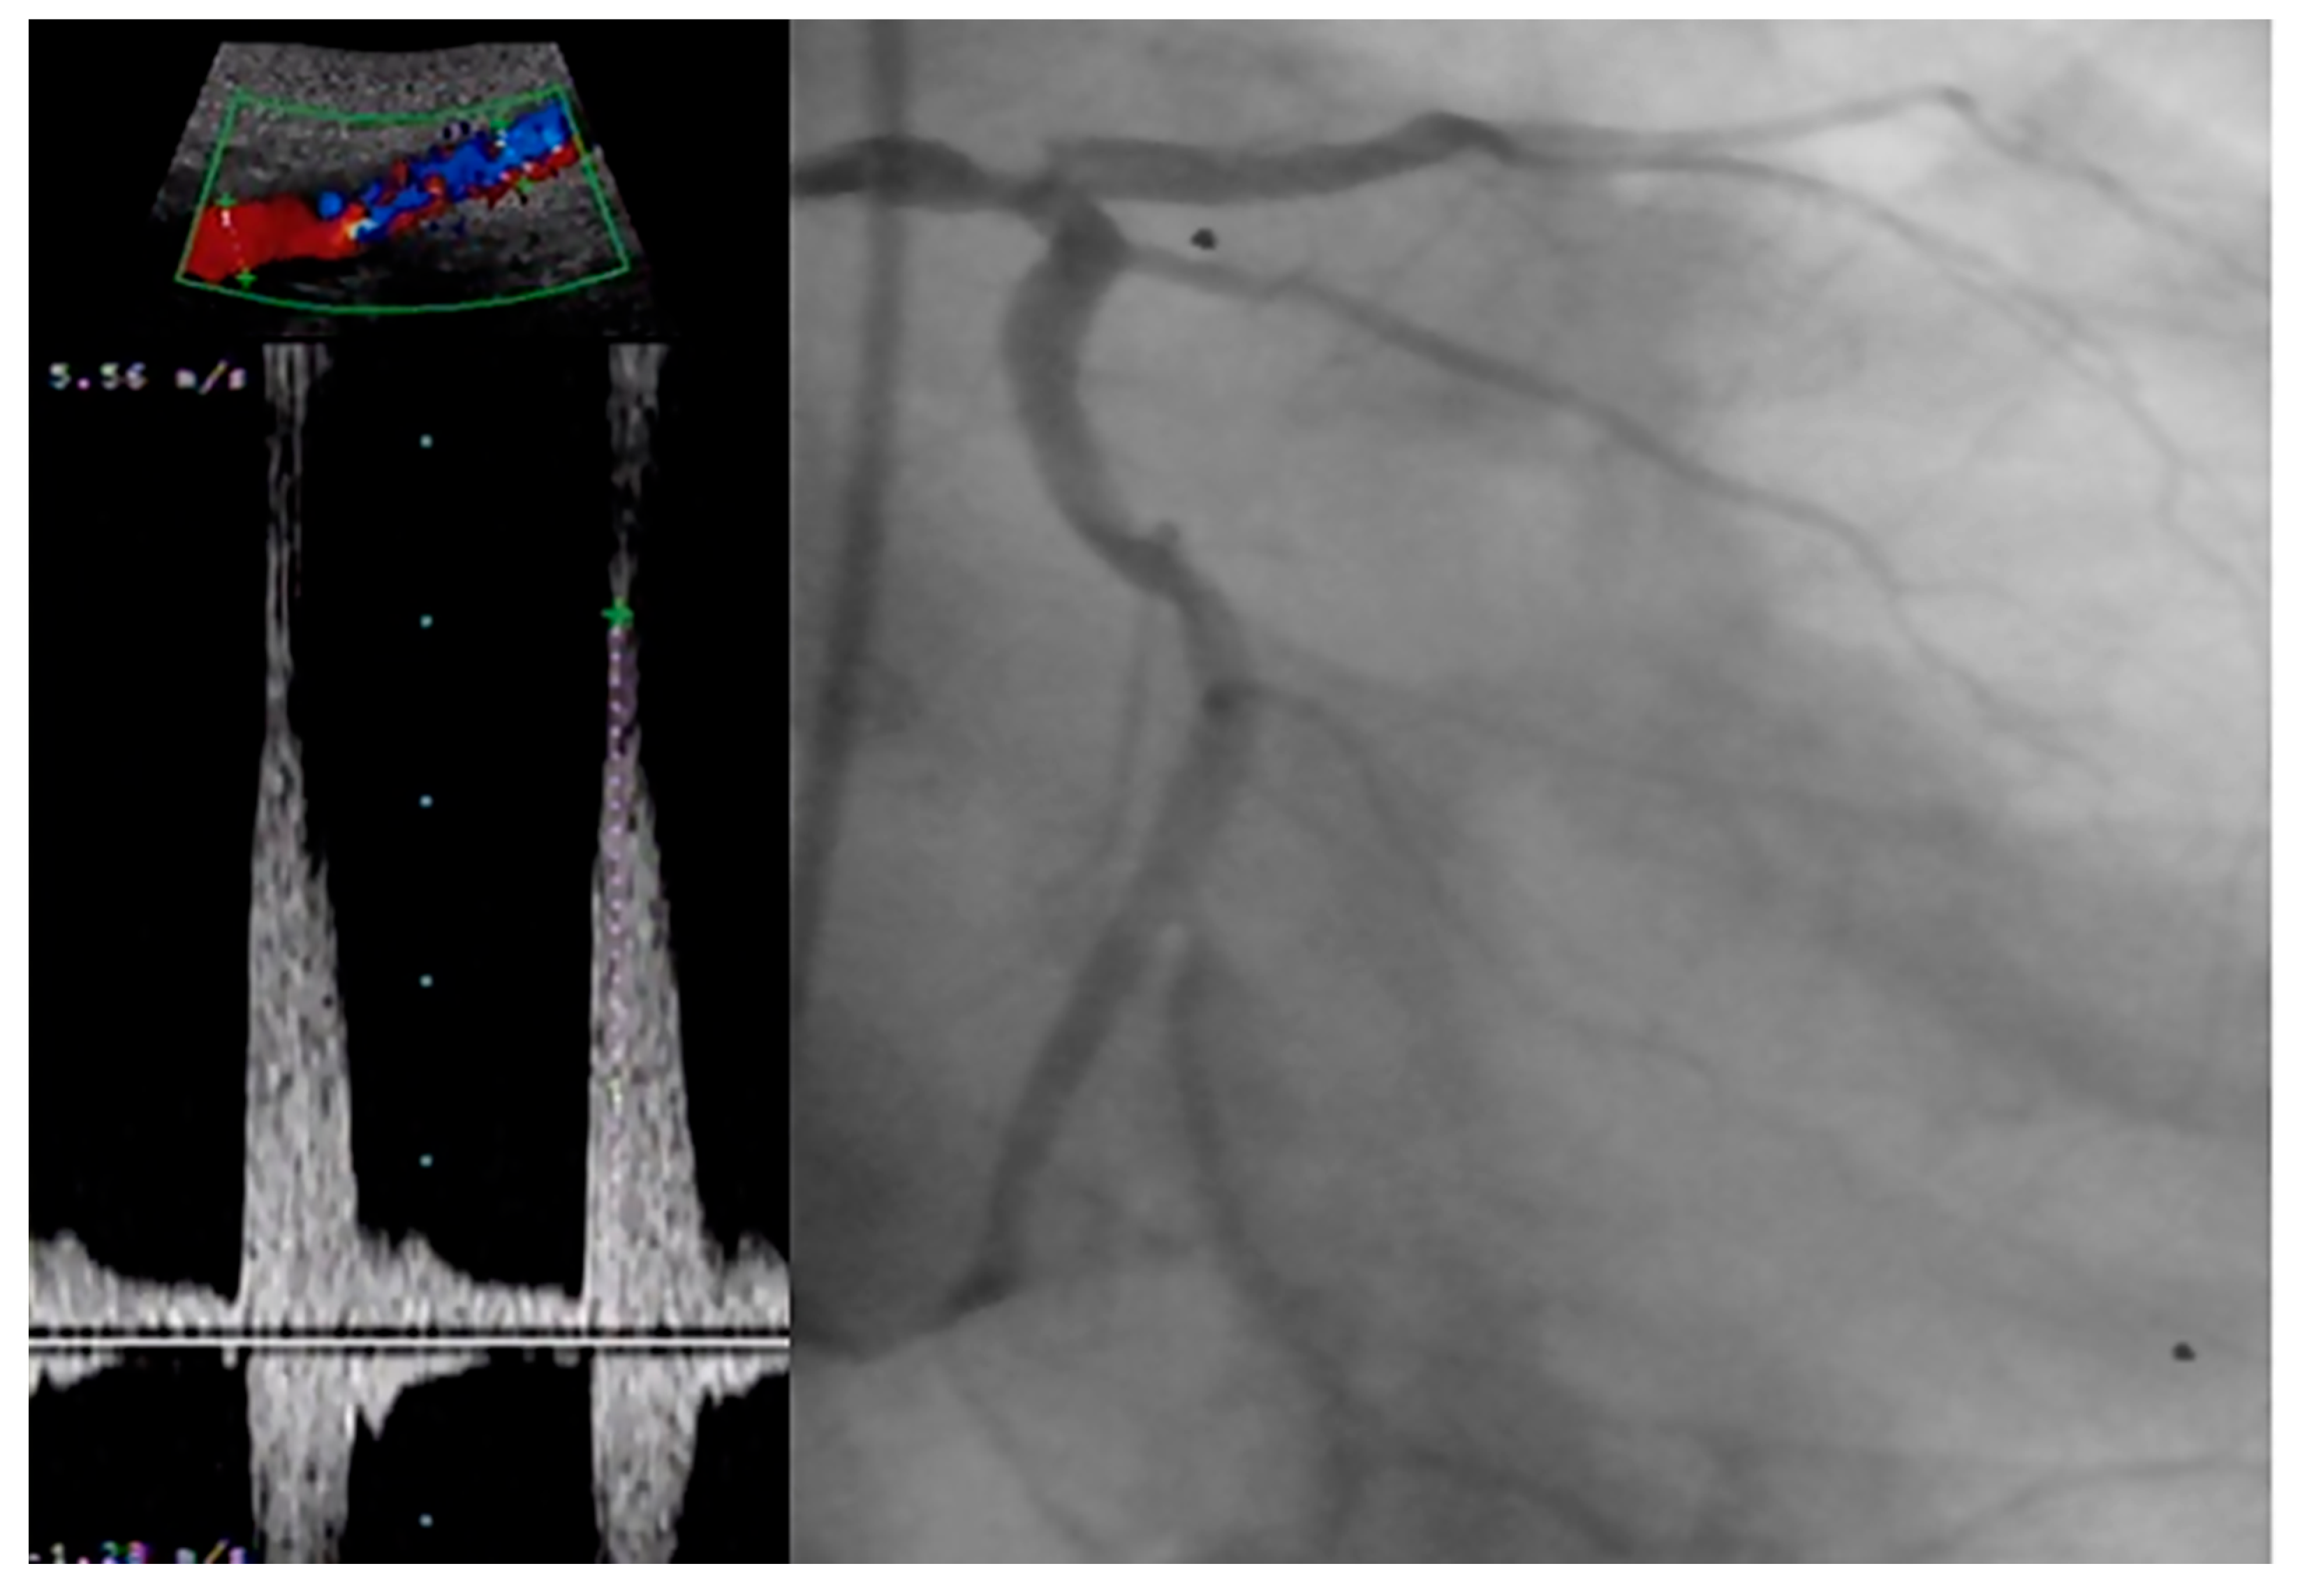

- Tătaru, D.A.; Olinic, M.; Homorodean, C.; Ober, M.C.; Spînu, M.; Lazăr, F.L.; Onea, L.; Olinic, D.M. Correlation between Ultrasound Peak Systolic Velocity and Angiography for Grading Internal Carotid Artery Stenosis. J. Clin. Med. 2024, 13, 517. [Google Scholar] [CrossRef] [PubMed]